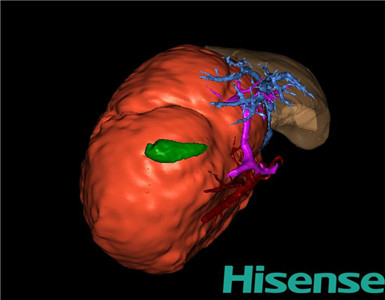

术前三维重建及手术方案设计:

将0.625mm双源薄层CT资料的静脉期和动脉期Dicom格式文件导入海信CAS系统。

通过调节窗宽窗位调整CT序号,对肝实质,胆囊,下腔静脉,肿瘤,肝动脉、门静脉及肝静脉等进行三维重建;系统自动计算肝脏体积。

模拟手术操作,自动计算切除肝体积、肿瘤体积、剩余功能性肝体积。

肝脏体积为218.1ml,肿瘤体积为1570ml,肿瘤体积为肝脏体积的7.2倍,通过比对1-3月正常肝脏体积为174.85±58.11ml,通过术前模拟手术,精准判断切除后剩余肝脏体积能耐受,避免肝衰竭发生。

术前三维重建:

重建图片